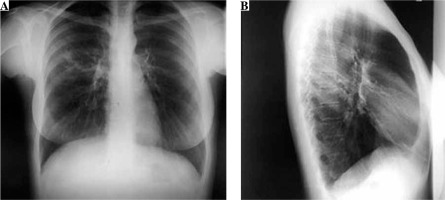

A 31-year-old woman was admitted to the hospital for the treatment of newly diagnosed drug-resistant (pre-extensively drug resistant) pulmonary tuberculosis (chest X-ray at time of diagnosis – Fig. 1). She was treated with second-line antituberculosis drugs: moxifloxacin, kanamycin, cycloserine, prothionamide, para-aminosalicylic acid. After 3 weeks of therapy she developed high fever (> 39°C), lymphadenopathy in the cervical and axillary regions and pruritic maculopapular eruption all over the body (Fig. 2). Hematologic abnormalities such as leukocytosis with eosinophilia (1.81 × 109/l) and monocytosis (1.85 × 109/l) were detected in peripheral blood of the patient. Hepatitis was asymptomatic and detected by the evaluation of liver function: serum aspartate aminotransferase (AST) 1379 IU/l and alanine aminotransferase (ALT) 1221 IU/l; levels of liver enzymes were increased by approximately 30-40-fold above the normal limits. The positive diagnosis of Epstein-Barr infection was based on the onset of increase in the anti-Epstein-Barr immunoglobulin (Ig) G titer (> 200 U/ml), implicating Epstein-Barr virus re-activation. Based on the clinic and laboratory findings diagnosis of DiHS/DRESS was suspected, and all the drugs were discontinued. Symptoms and laboratory abnormalities gradually resolved over 4 weeks without additional treatment.

Fig. 1

Chest X ray posterior-anterior view (A) and right lateral view (B) on admission. On the superior lobe posterior segment of the right lung a mild parenchymal opacity with several nodules can be seen